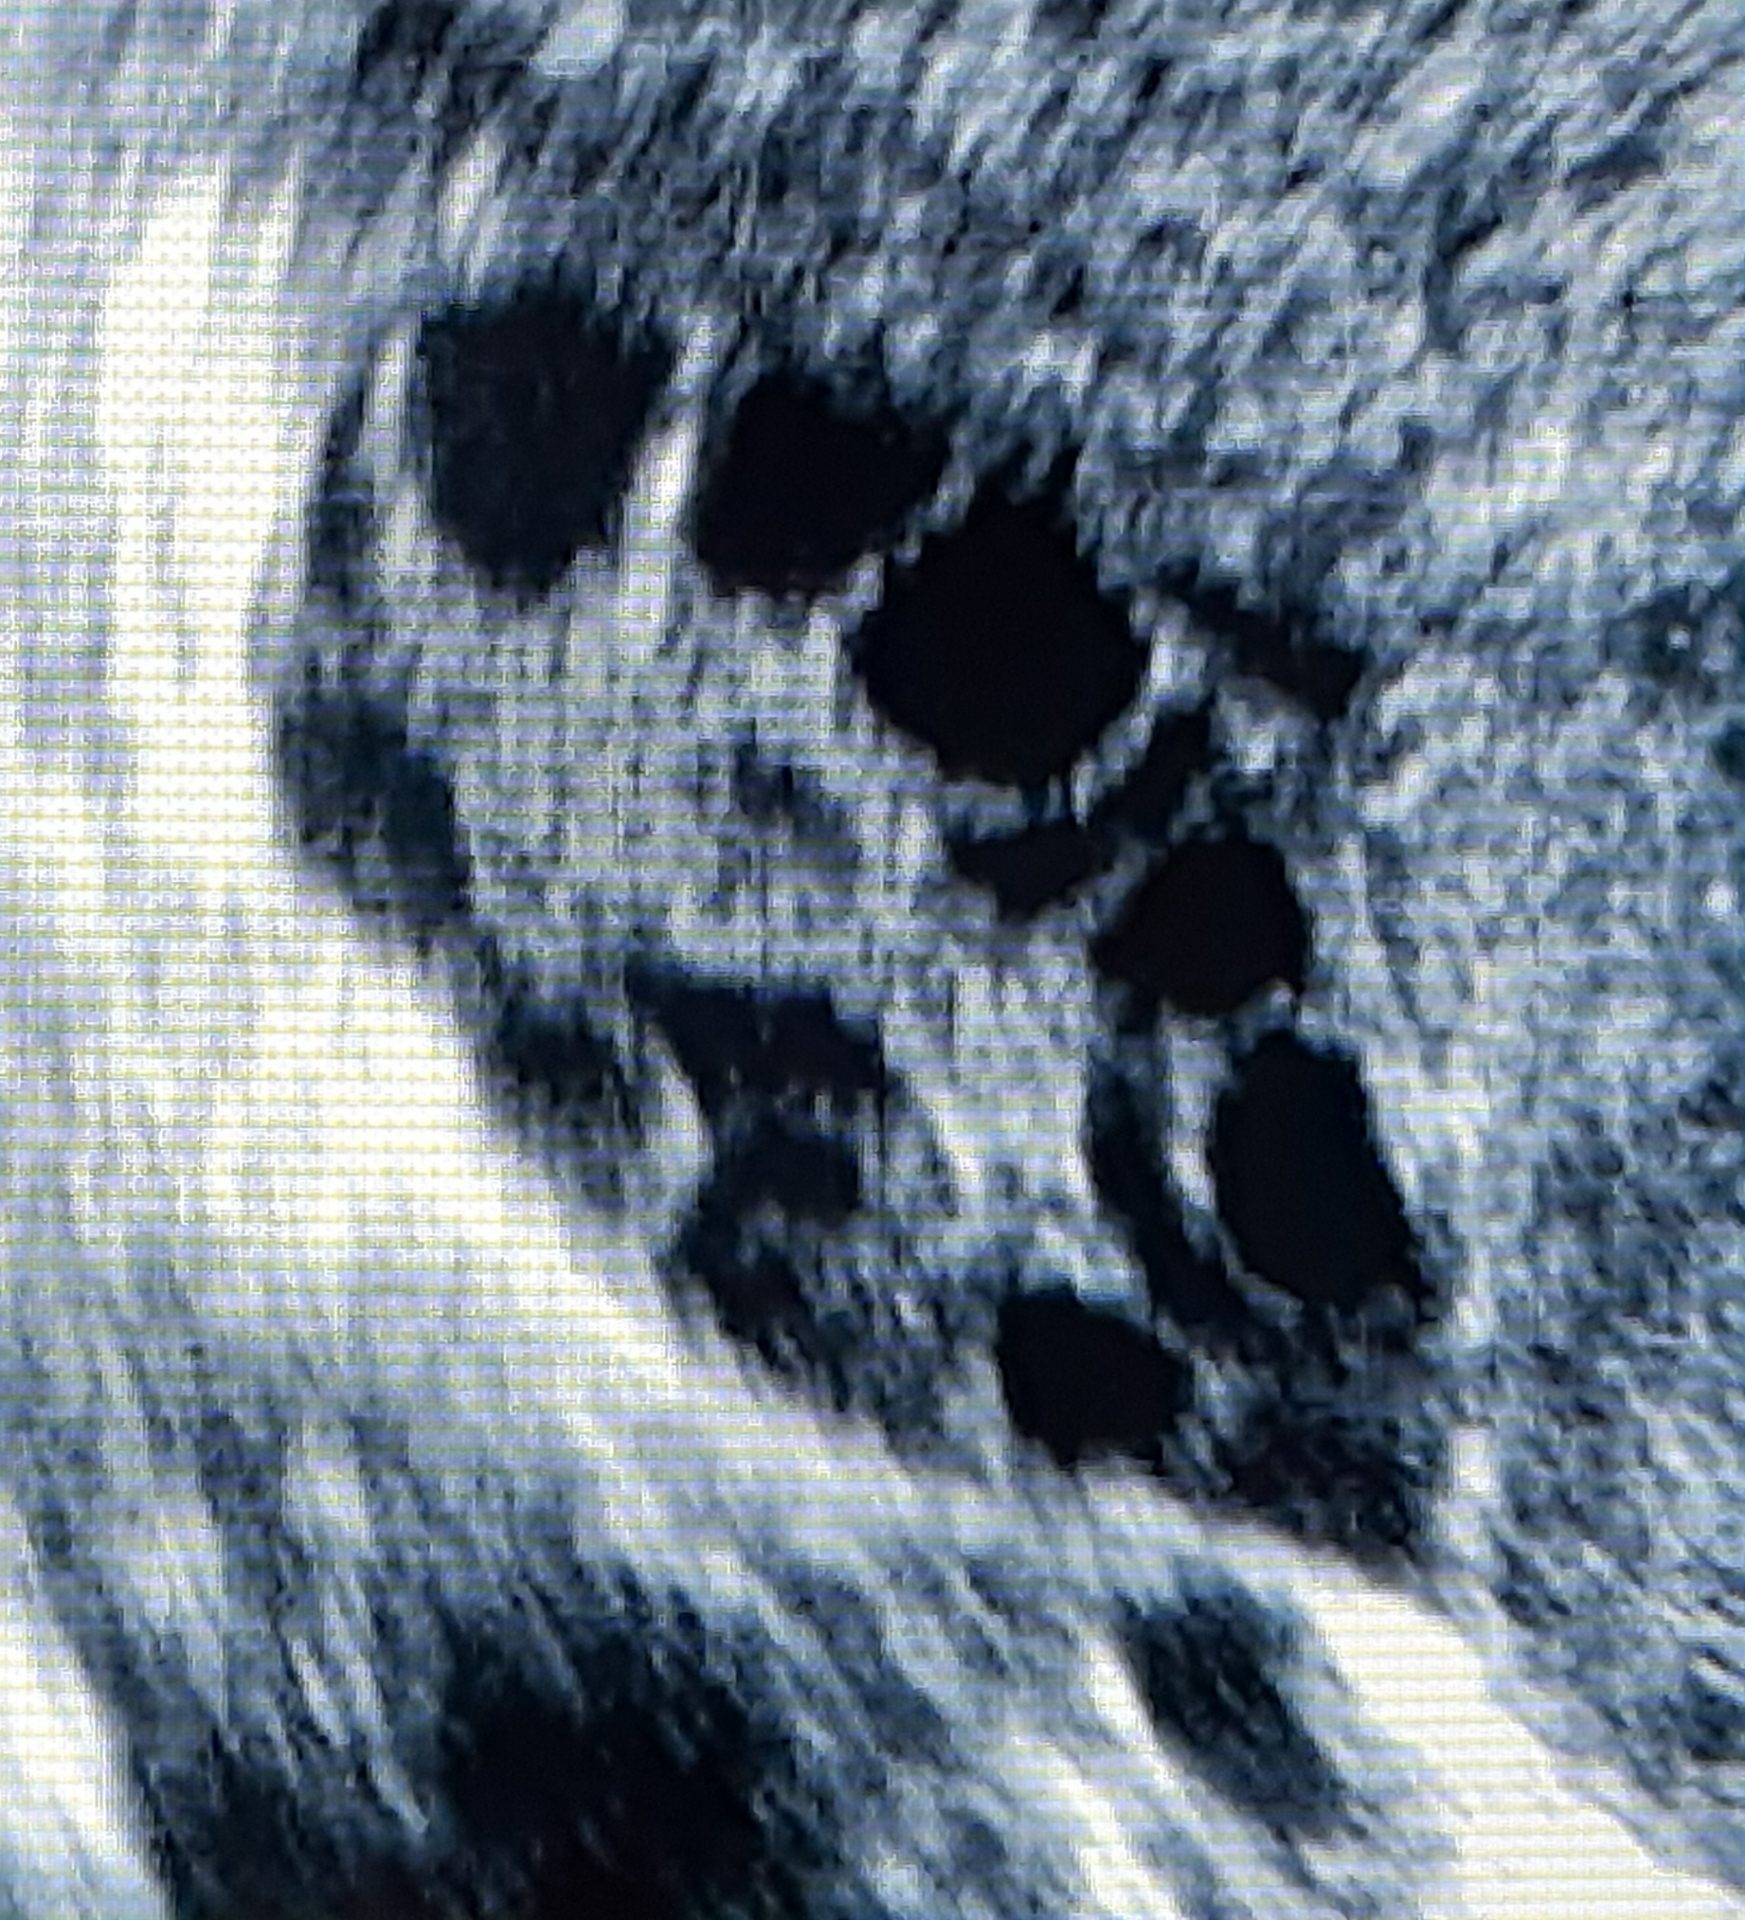

El síndrome de ovarios poliquísticos consiste en la aparición de varios pequeños quistes en el interior de los ovarios, lo cual es causado por una pérdida en el equilibrio hormonal a expensas de hormonas masculinas (andrógenos), los cuales dificultan que los ovarios liberen óvulos maduros que le permitan a la mujer alcanzar su periodo fértil del mes.